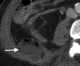

Fournier gangrene

Fournier gangrene is a type of necrotizing fasciitis or gangrene affecting the external genitalia or perineum. It commonly occurs in older men, but it can also occur in women and children. [Source: Wikipedia ]